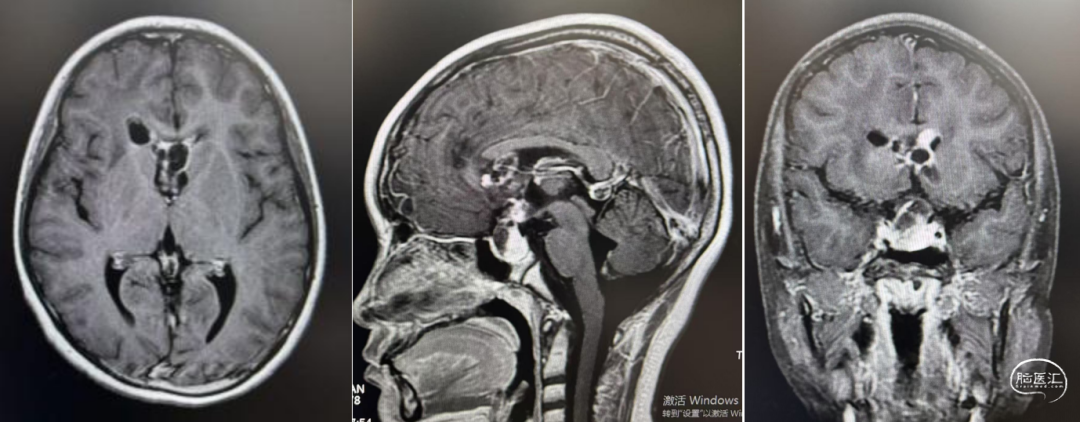

实验室检查:甲胎蛋白(AFP):3.535ng/ml,参考范围(0-10);人绒毛膜促性腺激素(β-HCG):163.0mIU/MI,参考范围(0-2)。

经儿童脑肿瘤MDT讨论后,考虑生殖细胞肿瘤,建议先化疗再放射治疗。1疗程后病变明显退缩。结疗后复查,肿瘤基本消失。此后3年予以定期复查未见复发。

结疗3年后随访